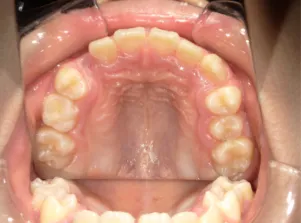

治療中③中1:拡大・前歯の並替え、トイシャー(出っ歯を治す装置)終了

*出っ歯、過蓋咬合、口唇閉鎖不全の改善

*咬合治療用モノブロック装置(筋機能的咬合誘導装置)へ移行

*口唇閉鎖不全がなおり奇麗な口元に改善

*就寝時に使用するモノブロック装置(筋機能的咬合誘導装置)